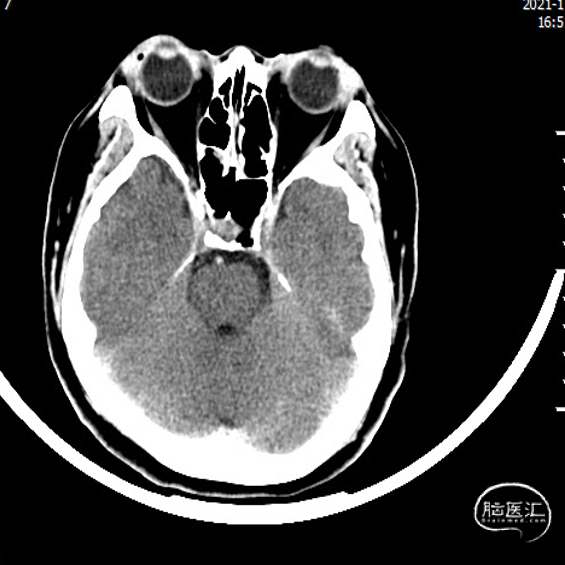

术前影像学检查

颅颈部CTA:右侧大脑中动脉局限性瘤样扩张伴其近远端管腔狭窄。

1. 右侧大脑中动脉M1段夹层动脉瘤

脑血管造影:右侧大脑中动脉M1段局部瘤样突起,远端重度狭窄,考虑右侧大脑中动脉M1段夹层动脉瘤。